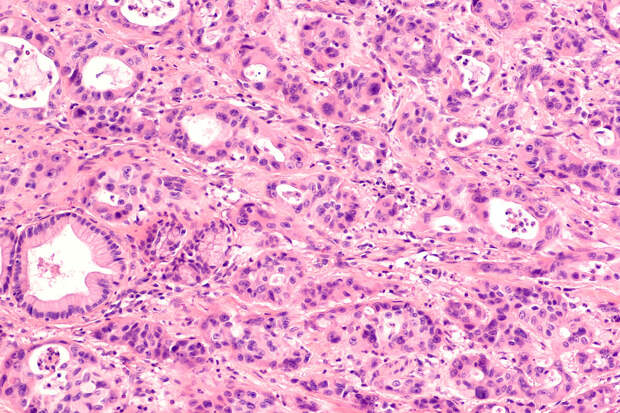

Американские ученые из Калифорнийского университета в Сан-Франциско обнаружили ключевой механизм, позволяющий раковым клеткам поджелудочной железы выживать в разных органах. Открытие может привести к новым методам лечения этого агрессивного типа рака. Исследование опубликовано в научном журнале Nature.

Команда выяснила, что белок белок PCSK9 играет решающую роль в способности раковых клеток метастазировать. В печени, где много холестерина, клетки с низким уровнем PCSK9 поглощают его из окружающей среды. В легких, где холестерина мало, клетки с высоким уровнем PCSK9 вырабатывают его сами и защищаются от кислородного повреждения.